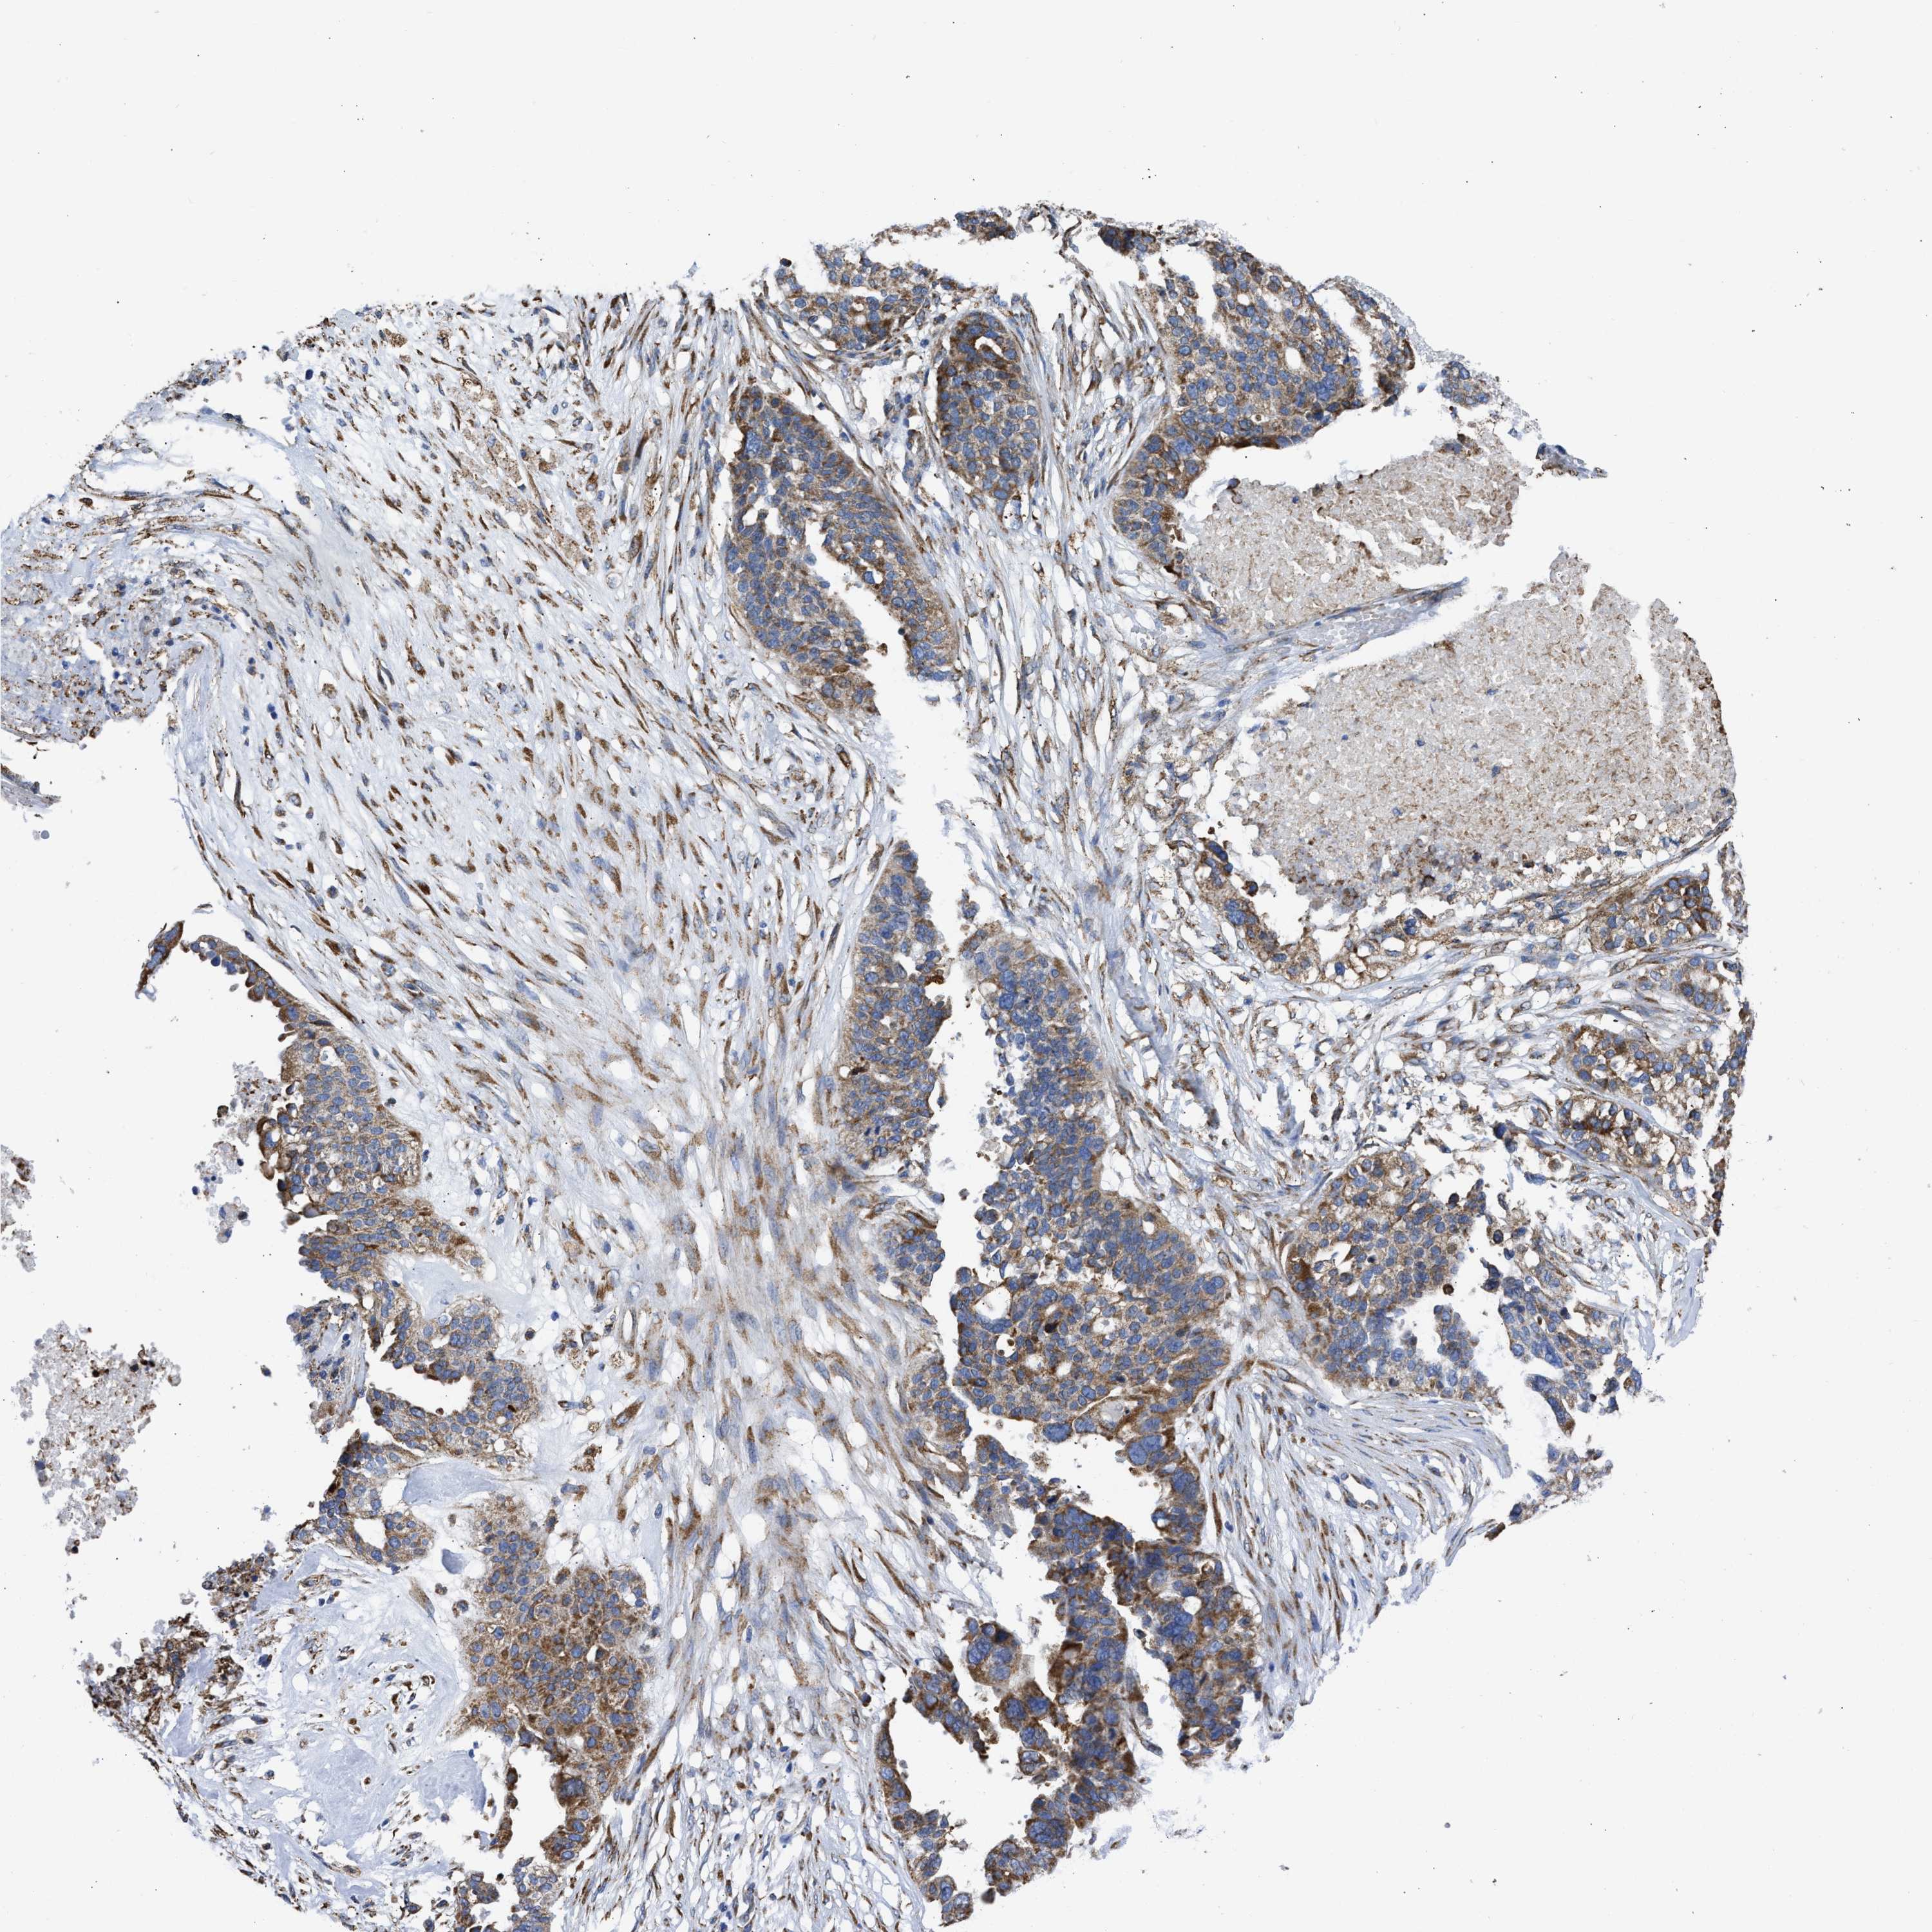

OVARIAN CANCER - Protein expressioni

A mouse-over function shows sample information and annotation data. Click on an image to view it in a full screen mode. Samples can be filtered based on level of antibody staining by selecting one or several of the following categories: high, medium, low and not detected. The assay and annotation is described here.

Note that samples used for immunohistochemistry by the Human Protein Atlas do not correspond to samples in the TCGA dataset.

Antibody stainingi

Antibody staining in the annotated cell types in the current human tissue is reported as not detected, low, medium, or high, based on conventional immunohistochemistry profiling in selected tissues. This score is based on the combination of the staining intensity and fraction of stained cells.

Each image is clickable and will lead to virtual microscopy that enables deeper exploration of all samples and also displays staining intensity scores, fraction scores and subcellular localization as well as patient and tissue information for each sample.

Antibody CAB004222

Antibody CAB005126

Antibody CAB018597

Cystadenocarcinoma, serous, NOS